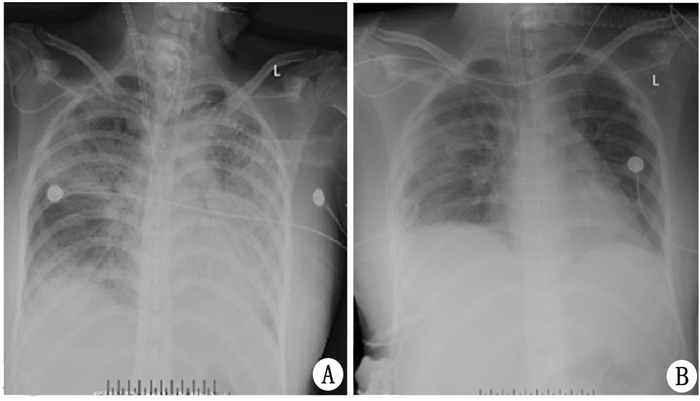

病例2患者,女,17岁,此次患病前身高157 cm, 既往患抑郁症1年余,因“误服药物后意识障碍、呼吸困难13 d”于2017年4月28日入院。2017年4月15日因误服抗精神病(具体名称及剂量不详)后出现意识障碍,轻度躁动,言语混乱,约30 min后送至当地医院给予洗胃,意识障碍仍加重,呼吸困难伴低氧血症,立即给予气管插管接呼吸机辅助呼吸,血液药物浓度检测示:喹流平1.3 μg/mL,文拉法辛1.1 μg/mL,米氮平0.6 μg/mL,给予“氟马西尼、纳美芬、哌拉西林他唑巴坦针”及维护器官等对症支持治疗,患者意识渐转清,4月18日患者出现意识障碍再次加重,呼吸无力、氧饱和度下降,复查胸部CT、感染指标提示双肺炎症加重,更改抗生素为“美罗培南、万古霉素”,感染指标稍好转,但呼吸困难加重、呼吸机支持(控制通气,潮气量500mL,PEEP 18 cmH2O,FiO2 80%)加大的情况下SpO2仍然难以维持在90%以上;4月26日颈部及前胸部出现皮下气肿,给予“左侧锁骨下皮下气肿切开引流术+气管切开术”,进一步调整呼吸机参数、增强呼吸支持后,SpO2维持在90%左右,但渐出现血压下降,需应用升压药维持血压,心率140次/min左右;急请我院会诊考虑存在重症肺炎、急性呼吸衰竭、ARDS,我急诊重症医师及ECMO团队,给予救护车上ECMO应用下转运至我院。入院后查体:患者神志昏迷,GCS评分E3VTM5,气管切开接呼吸机辅助呼吸(压力控制通气,PEEP 10 cmH2O,FiO2 60%,呼吸频率15次/min,PC above PEEP 15 cmH2O),监测潮气量180 mL左右,ECMO应用下SpO2维持在95%左右,颈部及胸壁皮肤有握雪感,左锁骨下方有一长约5 cm横行纱布覆盖切口,双侧瞳孔等大等圆,直径3 mm,对光反射迟钝,呼吸运动减弱,双肺呼吸音明显降低,未闻及干湿啰音,心率120次/min,律齐,余心脏、腹部、神经系统未见明显异常;入院后化验示:PaO267.1 mmHg,PaCO242.0 mmHg;白细胞数26.70×109/L; PCT2.380 ng/mL;白蛋白23.7 g/L;BNP3 797.0 pg/mL;胸片示:两肺纹理增粗,肺内多发大片状高密度影(图 3A);患者肺功能极度衰竭,持续ECMO应用(转速3 000转/min,氧流量5 L/min)替代肺功能,下调呼吸机调节参数、严格控制气道压30 cmH2O以下、防止肺部气压伤加重,PEEP 10 cmH2O左右维持肺开放,并给予“美罗培南、利奈唑胺、伏立康唑”抗感染、低剂量阿奇霉素、甲泼尼松龙防止肺纤维化及保护脏器等对症支持治疗,至5月5日PaO2逐渐上升为93.7 mmHg;PaCO241.4 mmHg;白细胞数8.50×109/L; PCT为1.500 ng/mL,白蛋白41.9 g/L;但潮气量上升不明显,200 mL左右,肺顺应性仍极差;5月9日患者右侧胸腔出现气胸,气胸量约75%,行“右侧胸腔闭式引流术”,5月12日观察胸腔闭式引流管中无气泡引流后给予拔除,氧合及胸片可见肺部情况渐好转,肺顺应性改善,潮气量逐渐升为400 mL左右,氧合指数大于300 mmHg, 5月20日给予逐渐下调ECMO氧流量,患者动脉血氧分压无明显下降,5月21日ECMO应用23 d后给予撤离。5月22日复查胸片肺部炎症明显改善(图 3 B),胸部CT示:双肺间质性改变(图 4 A );患者呼吸情况好转,逐步降低呼吸机支持并于5月28日脱机,后好转出院,随访(出院5周后胸部CT见图 4 B)至今无明显不适。

| A为转入我院时床旁胸片情况,可见双肺弥漫分布的片状浸润阴影,以左肺为甚。B为ECMO治疗3周后撤离ECMO前床旁胸片情况,右肺纹理稍粗,余肺野清晰 图 3 患者2胸片 |